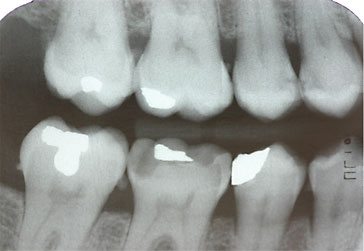

Zahnzwischenraumkaries

![]() |

Während Vorstufen einer Karies noch ohne invasive Eingriffe mittels Fluoridierungsverfahren behandelt werden können, werden kleinere kariöse Stellen vorzugsweise mit minimalinvasiven Präparationstechniken besonders substanzschonend versorgt. Dabei ist nicht allein die klein ausfallende Füllung, sondern die streng defektbezogene Kariesentfernung von Bedeutung.